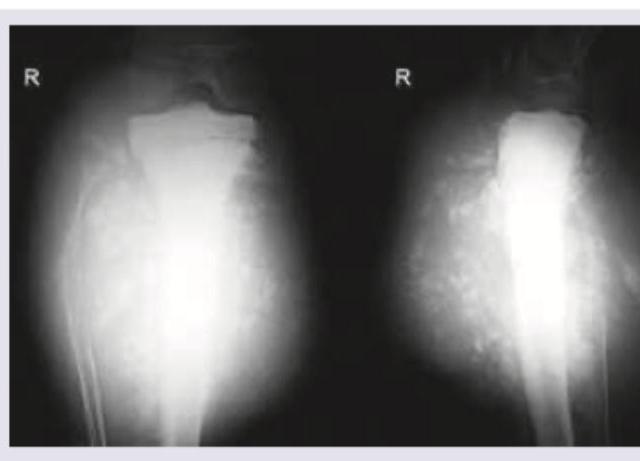

A 20-year-old college girl presents with pain in the upper part of tibia especially after dance classes. The pain has increased to a level that she cannot practice for forthcoming college festival. X-ray of the lower leg shows: